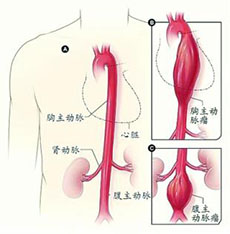

肺栓塞和下肢静脉血栓

疾病介绍:肺栓塞、肺动脉高压肺栓塞(pulmonary embolism, PE)是以各种栓子阻塞肺动脉系统为其发病原因的一组疾病或临床综合征的总称,以下肢静脉血栓脱落引起…【详细】

肺栓塞和下肢静脉血栓

疾病介绍:肺栓塞、肺动脉高压肺栓塞(pulmonary embolism, PE)是以各种栓子阻塞肺动脉系统为其发病原因的一组疾病或临床综合征的总称,以下肢静脉血栓脱落引起…【详细】

肺栓塞和下肢静脉血栓

疾病介绍:肺栓塞、肺动脉高压肺栓塞(pulmonary embolism, PE)是以各种栓子阻塞肺动脉系统为其发病原因的一组疾病或临床综合征的总称,以下肢静脉血栓脱落引起…【详细】

肺栓塞和下肢静脉血栓

疾病介绍:肺栓塞、肺动脉高压肺栓塞(pulmonary embolism, PE)是以各种栓子阻塞肺动脉系统为其发病原因的一组疾病或临床综合征的总称,以下肢静脉血栓脱落引起…【详细】

肺栓塞和下肢静脉血栓

疾病介绍:肺栓塞、肺动脉高压肺栓塞(pulmonary embolism, PE)是以各种栓子阻塞肺动脉系统为其发病原因的一组疾病或临床综合征的总称,以下肢静脉血栓脱落引起…【详细】

肺栓塞和下肢静脉血栓

疾病介绍:肺栓塞、肺动脉高压肺栓塞(pulmonary embolism, PE)是以各种栓子阻塞肺动脉系统为其发病原因的一组疾病或临床综合征的总称,以下肢静脉血栓脱落引起…【详细】

肺栓塞和下肢静脉血栓

疾病介绍:肺栓塞、肺动脉高压肺栓塞(pulmonary embolism, PE)是以各种栓子阻塞肺动脉系统为其发病原因的一组疾病或临床综合征的总称,以下肢静脉血栓脱落引起…【详细】